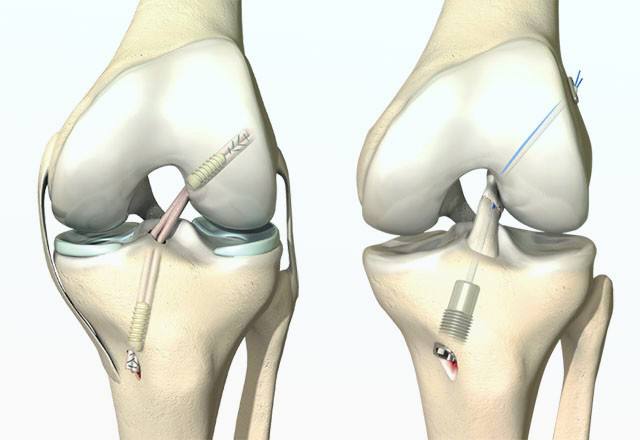

Artroskopiya

Bo'g'im kasalliklarini mini invaziv tekshirish va davolash

Butsimon boylam plastikasi

Tiz jarrohligi

Tiz bo'g'imi muammolarini zamonaviy titanium implantlar bilan davolash